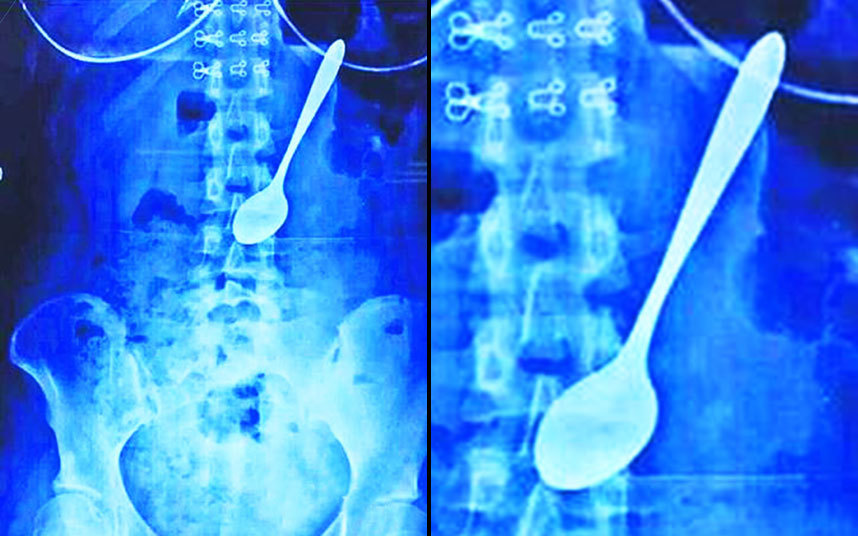

أشعة سينية تُظهر ابتلاع سيدة صينية لملعقة مسطحة في مدينة دونغقوان، كيف حصل هذا؟

أشعة سينية تُظهر ملعقة ابتلعتها سيدة خطأً أثناء تناول طعام الغداء!